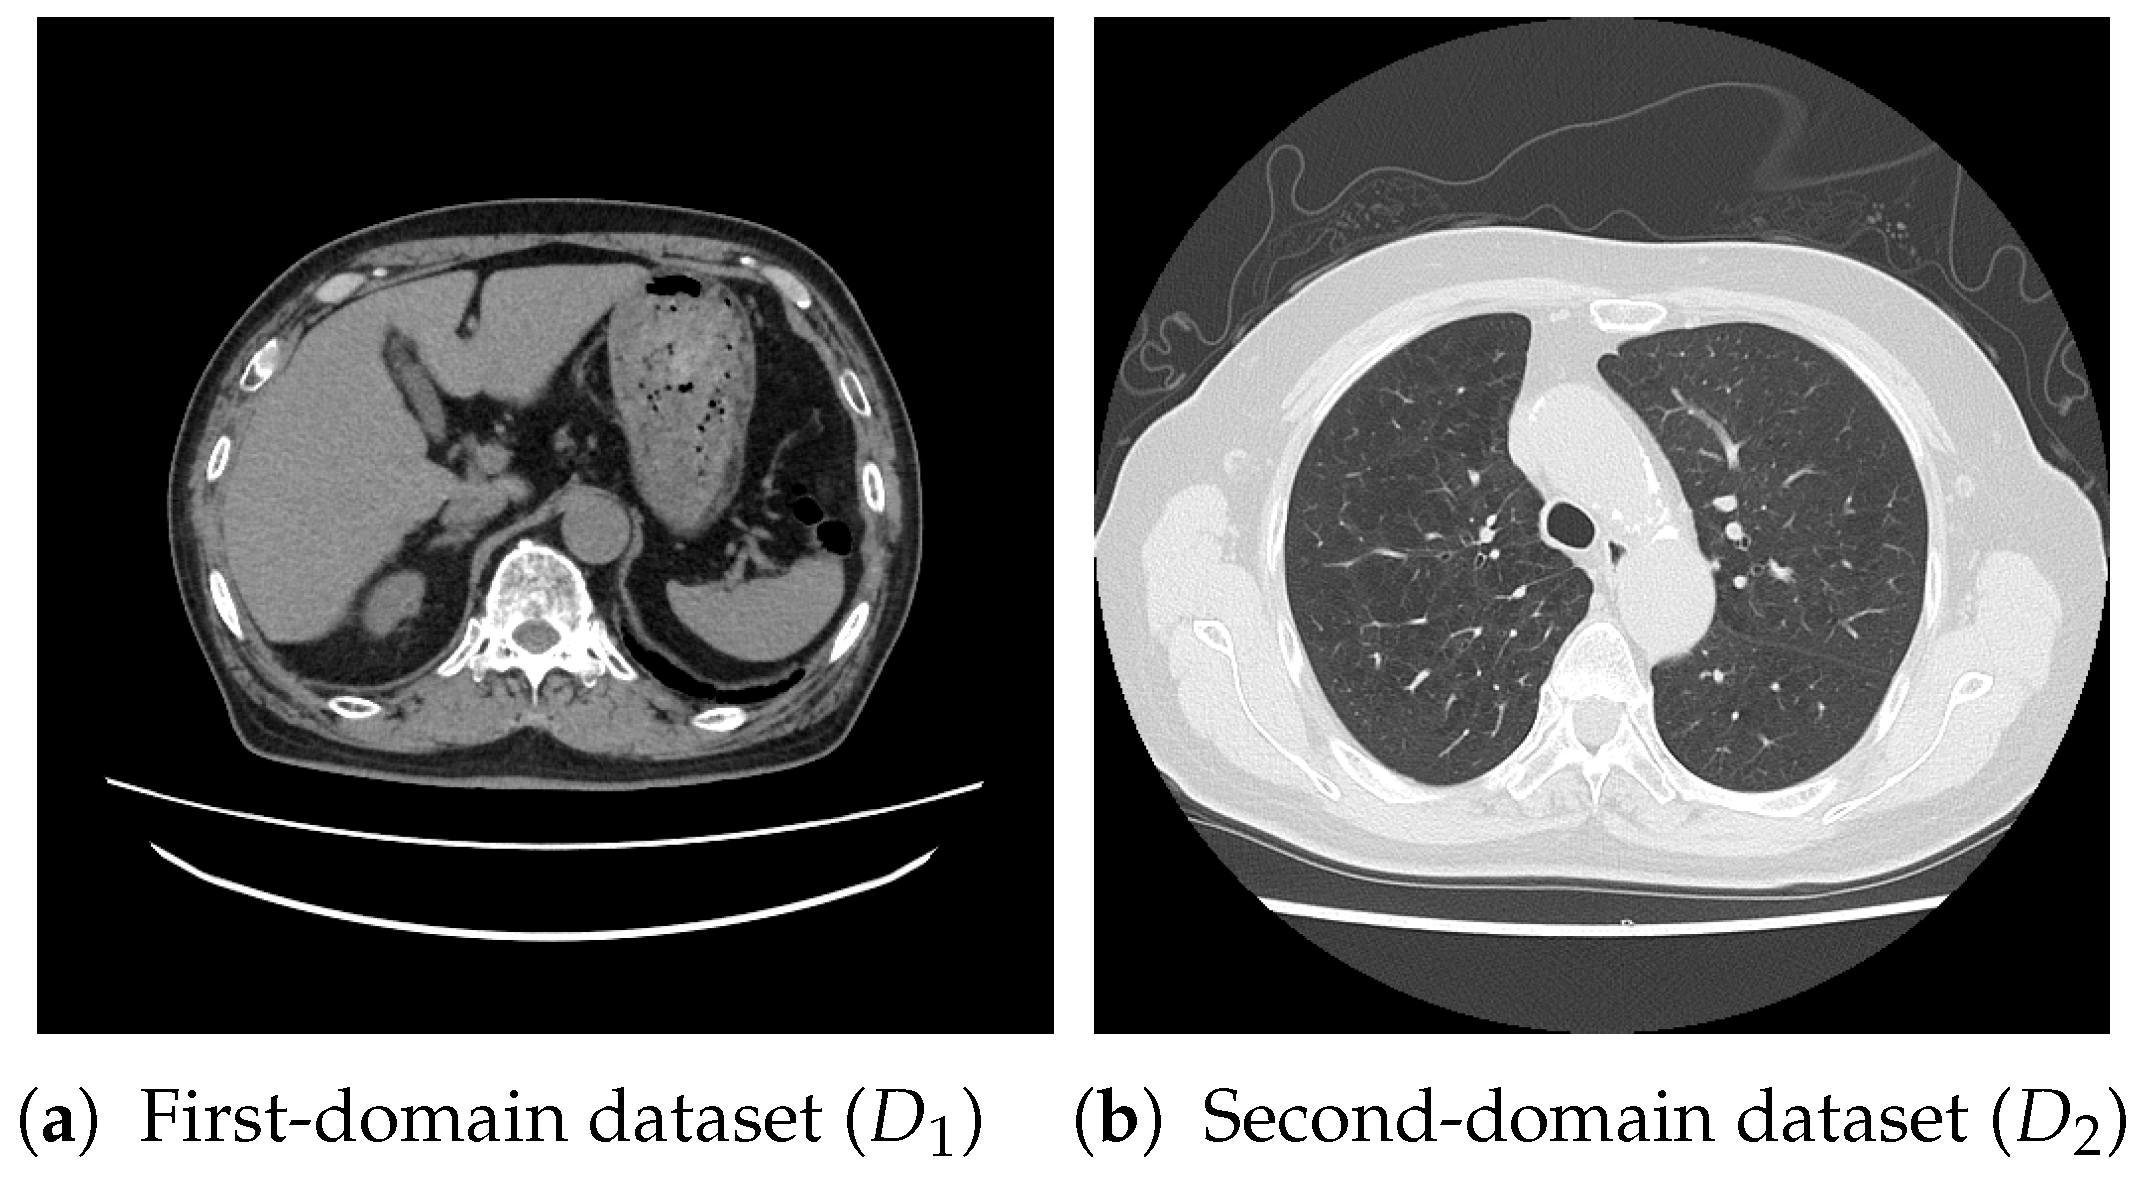

For pretraining, we utilized a subset of the J-MID (https://www.radiology.jp/j-mid/ (accessed on 6 April 2025)) database, which contains large-scale CT scans from Japanese medical institutions, and the RICORD dataset [58], an open dataset that was developed collaboratively by the Radiological Society of North America and international partners and contains chest CT scans collected from four countries. Each dataset was constructed with two domains based on mediastinal and lung window settings in chest CT images. Both domains are denoted as and , and the labels are not used during pretraining. Specifically, for the J-MID subset, (the mediastinal window) contains 31,256 CT images, and (the lung window) contains 26,403 CT images. The RICORD dataset comprises 12,897 (mediastinal window) images and 11,668 (lung window) images for pretraining. For the J-MID dataset, was generated using a window level (WL) of HU and a window width (WW) of HU, whereas was generated using a WL of HU and a WW of HU. For the RICORD dataset, was generated with a WL of HU and a WW of HU, while was generated with a WL of HU and a WW of HU. These parameter ranges were selected to cover clinically standard lung and mediastinal window settings while accommodating inter-scan variability in DICOM metadata. The corresponding images for each example are shown in Figure 2 and Figure 3. For fine-tuning and evaluation, we utilized two public datasets: the SARS-CoV-2 CT-Scan Dataset [59] and the Chest CT-Scan Images Dataset (https://www.kaggle.com/datasets/mohamedhanyyy/chest-ctscan-images (accessed on 6 April 2025)). Both datasets were used for the coronavirus disease 2019 (COVID-19) and chest cancer classification tasks, respectively. The data breakdown is as follows: the SARS-CoV-2 CT-Scan Dataset comprises 1589 training, 397 validation, and 495 test images, labeled into two (COVID-19 and Normal) classes. The Chest CT-Scan Images Dataset comprises 490 training, 123 validation, and 315 test images labeled into four (adenocarcinoma, large-cell carcinoma, squamous-cell carcinoma, and normal) classes. COVID-19 classification and lung cancer classification were selected as downstream tasks because chest CT is widely used in clinical practice for diagnosing both COVID-19 and lung cancer, allowing for an evaluation that closely reflects real-world clinical scenarios. Accordingly, to ensure reproducibility and enable fair comparisons with prior studies, we prioritized the use of publicly available datasets. The corresponding images for each example are shown in Figure 4 and Figure 5.

Figure 2.

Examples of chest CT images on the subsets from the J-MID database: (a) first-domain dataset () and (b) second-domain dataset ().